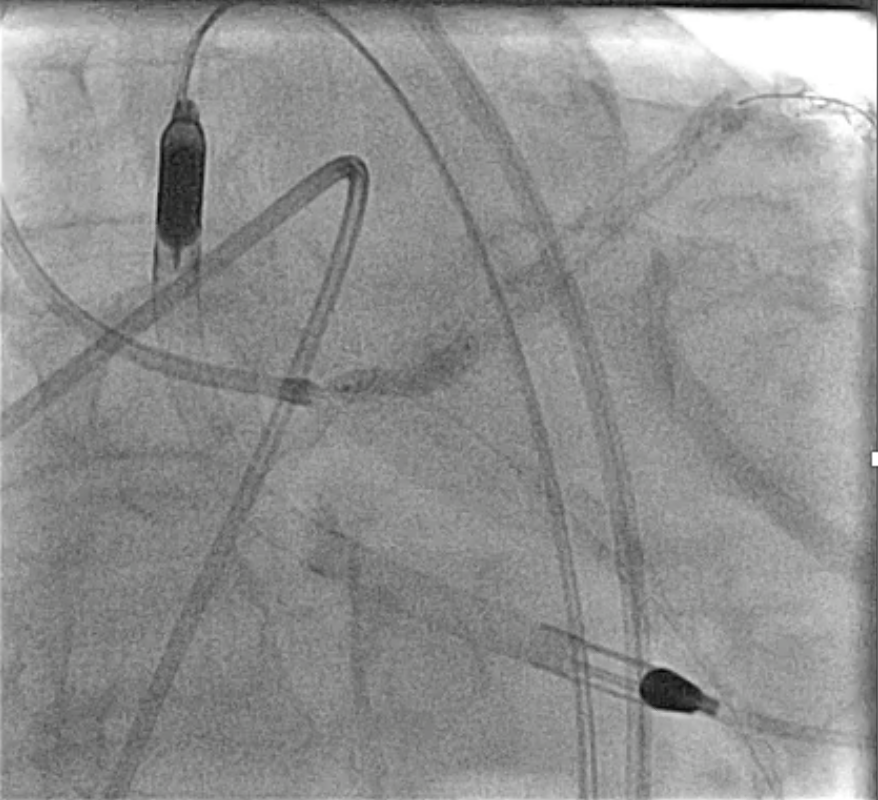

An Impella CP was inserted via the right femoral artery for hemodynamic support (baseline CI 2.07 L/min/m©÷, PCWP 34 mmHg). The LM was engaged with a 7 Fr EBU 3.5 guiding catheter. Angiography demonstrated heavily calcified distal LM bifurcation ISR with multiple stent layers extending into both LAD and LCX. Rotational atherectomy (RA) using a 1.5-mm burr was first attempted at the LAD-distal segment, but severe calcification prevented smooth burr passage even under Dyna mode. After changing to a 2.0-mm burr, the lesion was successfully crossed and adequately modified. Subsequently, the 1.5-mm burr was redirected for LCX lesion debulking, but burr entrapment occurred at the proximal LCX during the third run. Hemodynamics remained stable under Impella support. The burr was freed using a combination of deep seating a Guideplus ST for additional backup, small-balloon anchoring, and gentle forward–reverse rotation maneuvers. To ensure complete plaque modification, a 2.0-mm burr was used again to finalize both LAD and LCX runs. Cutting balloon angioplasty yielded suboptimal expansion; therefore, intravascular lithotripsy (IVL 3.5 mm, ≈40 pulses per ostium) was applied to achieve calcium fracture and full balloon compliance. Lesions were treated with DEB 4.0¡¿30 mm LM–LAD and 3.0¡¿30 mm LCX, followed by kissing balloon inflation. The Impella was removed uneventfully, and the patient recovered without hemodynamic compromise. Final angiogram showed well-apposed stents.